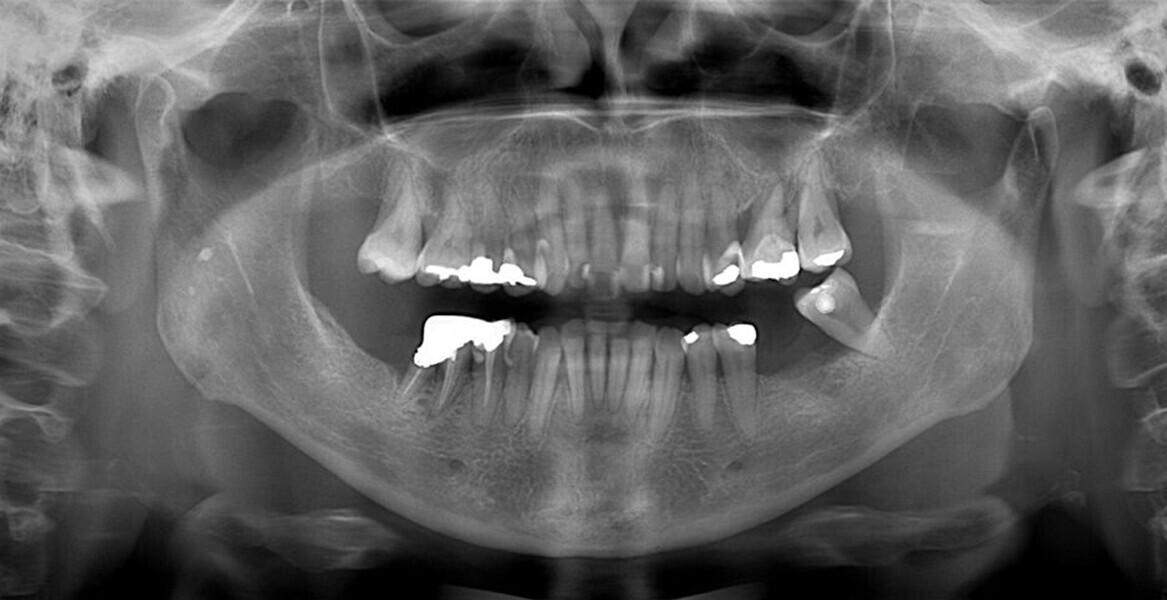

The periodontal treatment of an adult patient undergoing treatment with aligners is illustrated in demonstration of these points. Orthodontic planning considered the extra-oral photographs (Fig. 1) and intra-oral photographs (Figs. 2 & 3). Intra-oral scanning (Fig. 4) and radiographic documentation using panoramic radiographs and cephalometric radiographs (Figs. 5 & 6) were also carried out. From a periodontal perspective, periapical radiographs were recommended (Fig. 7), as this was an adult patient who smoked and showed clinical signs of advanced periodontal disease. Prior periodontal treatment was carried out (Fig. 8) to begin treatment with aligners (Fig. 9).